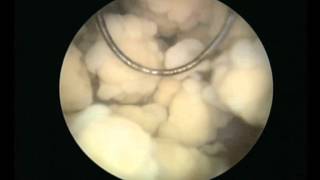

Μέθοδο TURis

Video Gallery